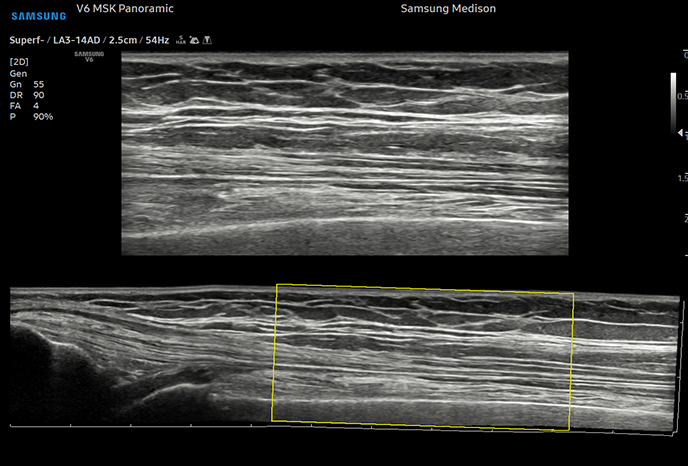

Samsung V6 Ultrasonic

• 01

고급 실시간 3D(4D)로 시각화 가능

• 02

고급 도플러 기능으로 심혈관 평가 및 이상 감지

• 03

이미지 해상도 극대화, 노이즈 최소화로 장기의 경계부를 선명하게 관찰

• 04

저강도 초음파 기술로 신체 조직 위험 최소화

• 05

연속적인 모니터링으로 고양이 심장초음파에 최적

촬영 부위

심장심장의 해부학 구조 및 혈류역학적 평가, 순환기계 장애, 심장 수축·이완

복부간담도계, 비장, 소화기계, 비뇨기계, 부신, 생식기계, 복강 림프절

근골격계근골격계 및 관절 인대

안구안구 내 구조 및 이상 확인

파노라마 영상